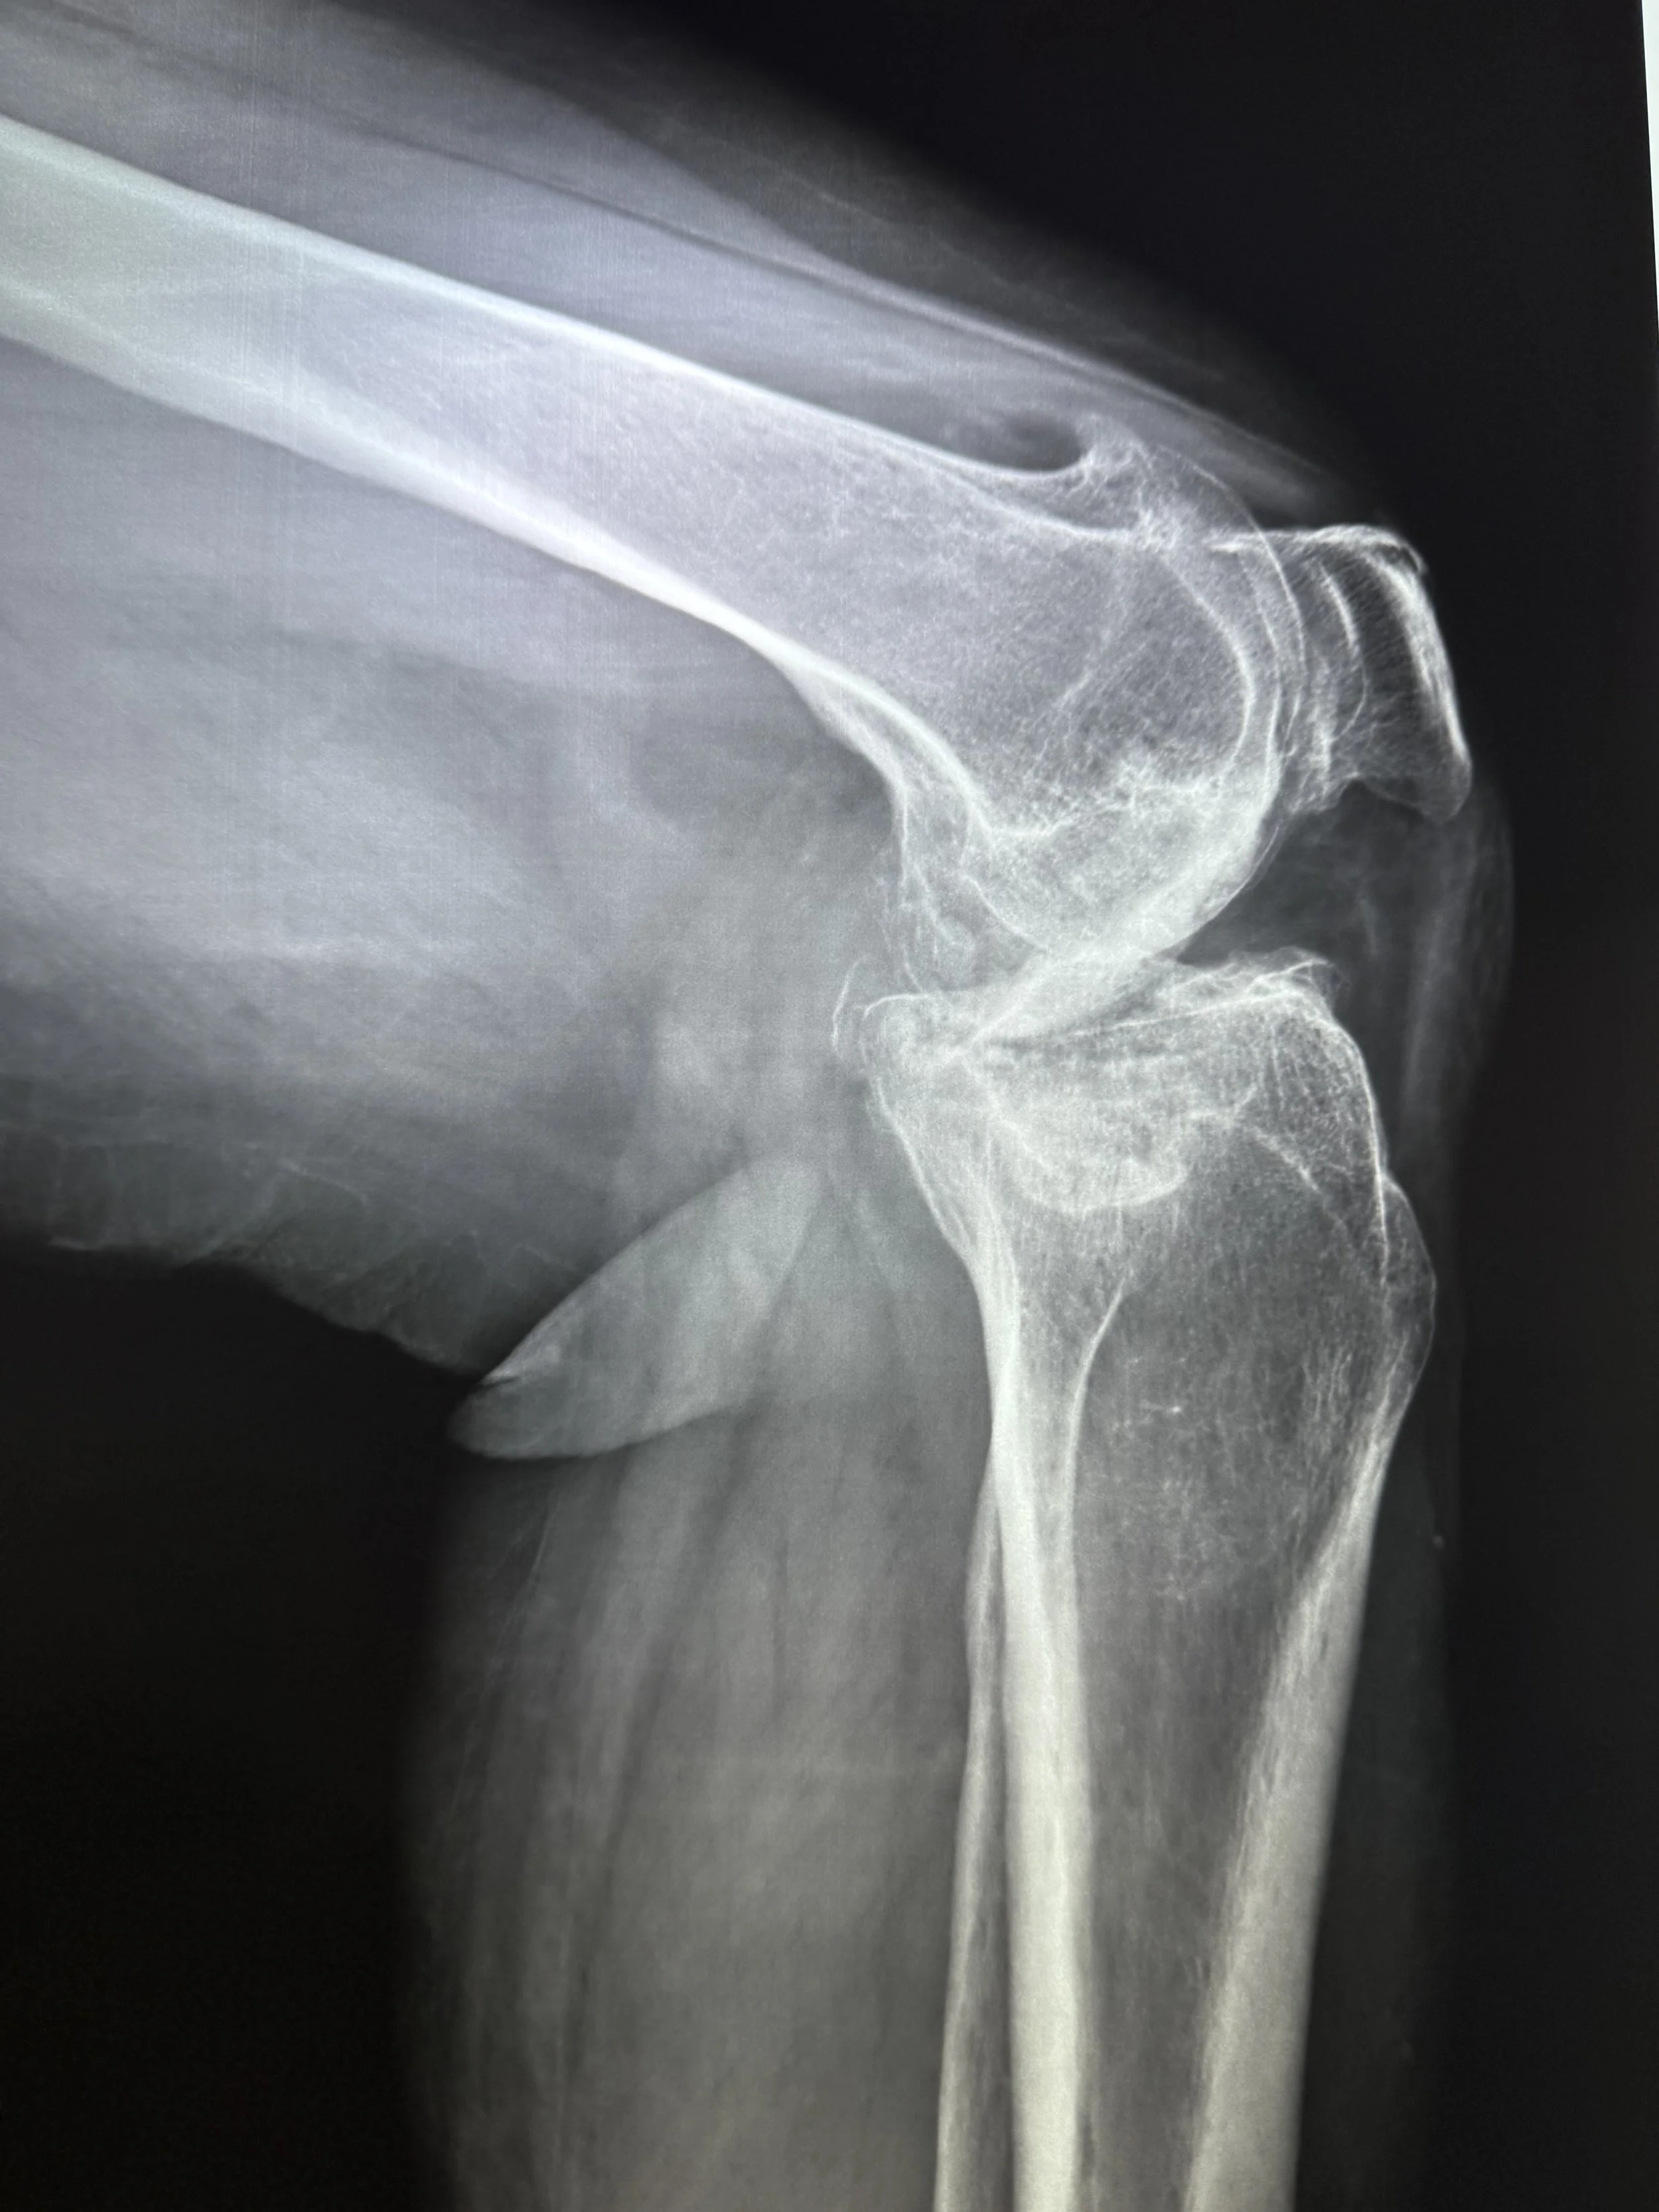

Today, we had the humble privilege of seeing over 100 patients in need of surgical care for hip, knee, foot, and ankle deformity. We will begin tomorrow with 6 operating rooms, 25 cases planned, 9 surgeons, 7 anesthesiologists, and 43 health care professionals working together.